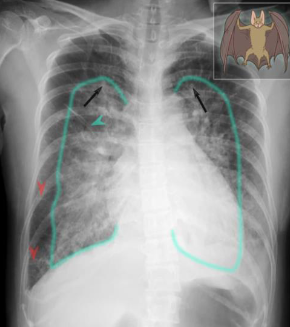

- Imaging examination X-ray chest (PA view)

- Findings or description

- The cardiac silhouette is enlarged

- upper lobe vessels are prominent

- Bilateral perihilar opacity batwing, or butterfly appearance.

- Thickened interlobular septae (Kerley lines)

- Diagnosis Pulmonary edema